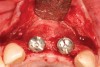

Figure 2  The orientation of the healing abutments after the patient had undergone extraction, guided bone regeneration, and implant placement. Note the wide spacing between the central incisor implants.

Figure 2

Figure 3  Periapical radiograph of implants in the Nos. 8 and 9 sites 3 years after placement. A bony peak was still present between the implants due to successful guided bone regeneration and favorable fixture spacing.

Figure 3

Figure 4  Final restoration of implants in the Nos. 8 and 9 sites 3 years after placement. Note the short central papilla regardless of the presence of bone. Restoration courtesy of Dr. Alan Goldberg.

Figure 4

Figure 5  A naturally low smile line hid the clinical “black triangle” from view.

Figure 5